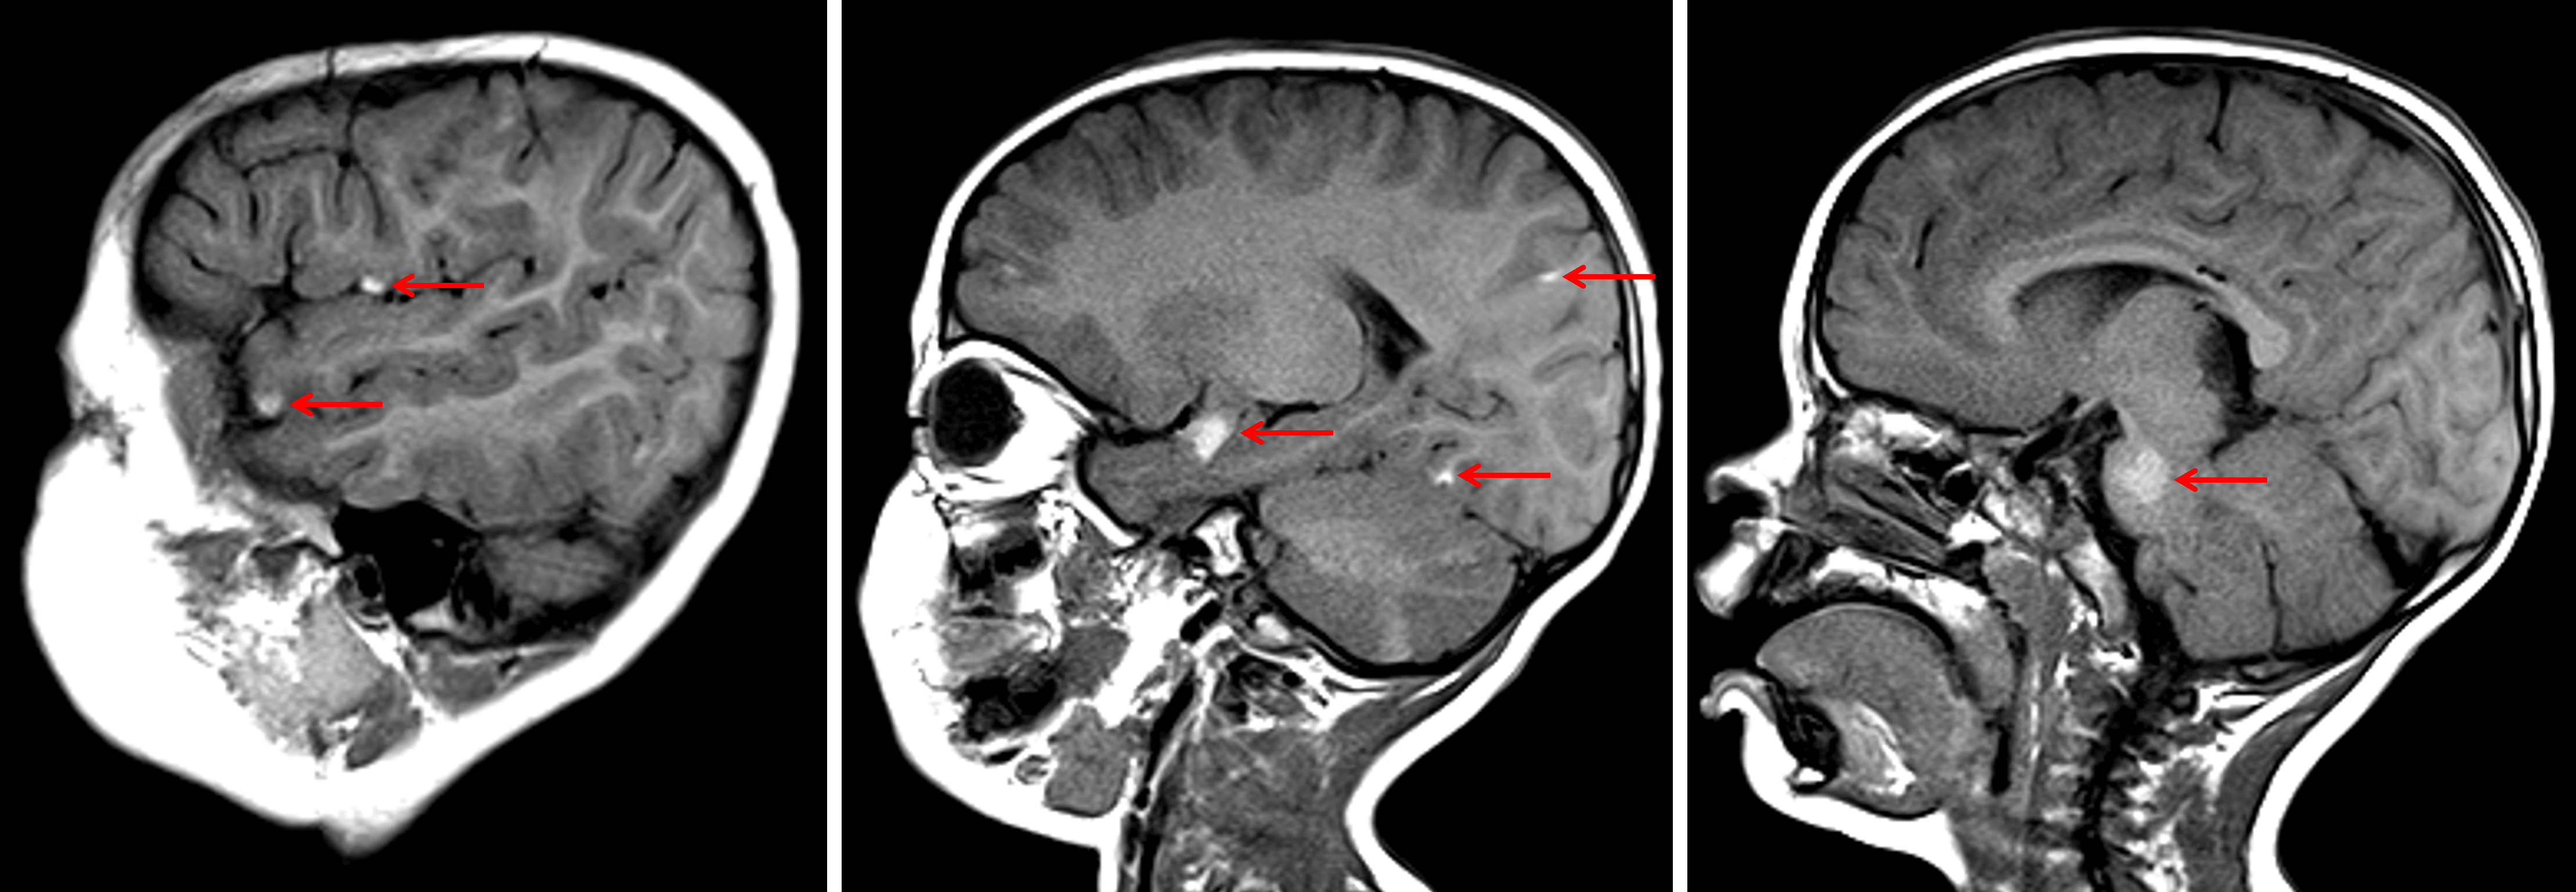

Multiple T1 hyperintense lesions scattered along the surface of the brain and brainstem (red arrows) in this patient with neurocutaneous melanosis.